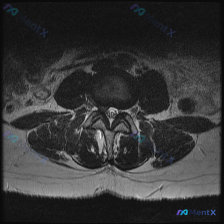

看到一张很典型的腰椎MRI轴位片,关于椎间盘病变的观察,整理了完整读片思路和分析,分享给大家。 病例影像基础信息 这是一张腰椎MRI的T2加权轴位图像,层面为腰椎间盘水平。 影像观察核心发现 1. 椎间盘结构:中心前方的椎间盘T2信号较正常髓核降低,呈灰黑色,提示椎间盘脱水退行性改变 2. 突出情况...